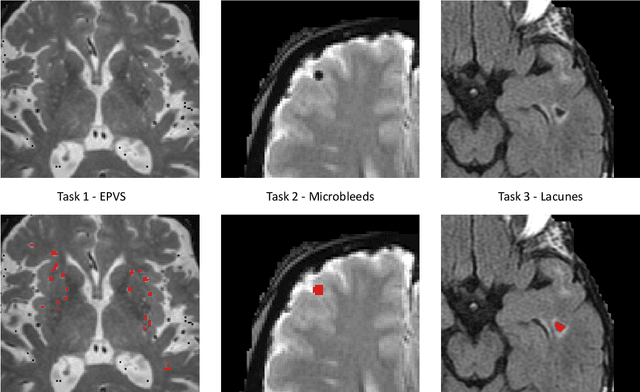

Abstract:Imaging markers of cerebral small vessel disease provide valuable information on brain health, but their manual assessment is time-consuming and hampered by substantial intra- and interrater variability. Automated rating may benefit biomedical research, as well as clinical assessment, but diagnostic reliability of existing algorithms is unknown. Here, we present the results of the \textit{VAscular Lesions DetectiOn and Segmentation} (\textit{Where is VALDO?}) challenge that was run as a satellite event at the international conference on Medical Image Computing and Computer Aided Intervention (MICCAI) 2021. This challenge aimed to promote the development of methods for automated detection and segmentation of small and sparse imaging markers of cerebral small vessel disease, namely enlarged perivascular spaces (EPVS) (Task 1), cerebral microbleeds (Task 2) and lacunes of presumed vascular origin (Task 3) while leveraging weak and noisy labels. Overall, 12 teams participated in the challenge proposing solutions for one or more tasks (4 for Task 1 - EPVS, 9 for Task 2 - Microbleeds and 6 for Task 3 - Lacunes). Multi-cohort data was used in both training and evaluation. Results showed a large variability in performance both across teams and across tasks, with promising results notably for Task 1 - EPVS and Task 2 - Microbleeds and not practically useful results yet for Task 3 - Lacunes. It also highlighted the performance inconsistency across cases that may deter use at an individual level, while still proving useful at a population level.